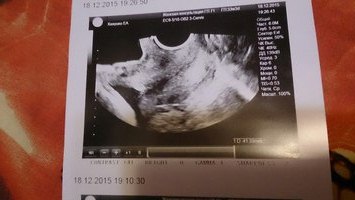

УЗИ, КТГ, доплерДали после последнего узи в ЖК снимок, только вот снимок чего, я так и не поняла)) Может кто-то здесь разбирается?

А вам про плаценты ничего не говорили? Просто похоже на мой снимок,делали чтобы посмотреть однородность,там вот как раз такие черные ядрышки.

Кхм...мне видится вид со спины,сверху справа голова(затылок) снизу слева попа)